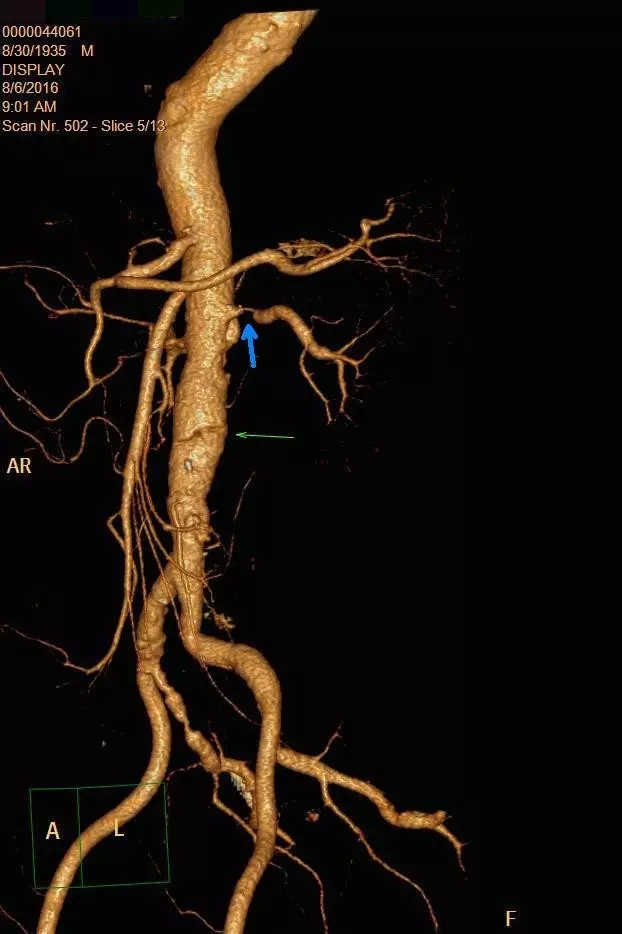

入院后,王兵教授及崔文军副主任医师高度重视,亲自与患者家属沟通病情,告知该病的严重性,并叮嘱患者绝对卧床休息,积极控制血压,保持大便通畅,同时指示主管医师王颖主治医师,积极完善主动脉CTA等检查。考虑到患者病情危重,为避免意外发生,王颖医师亲自陪同患者去CT室检查,CT室也积极配合,开通绿色通道急诊行CTA检查。很快结果出来了:腹主动脉夹层(图1)!同时发现双侧肾动脉狭窄,左侧肾动脉重度狭窄,几近闭塞(图2)。

图2

所幸的是,这次体检发现比较及时,夹层范围也相对较小,但体内的这个不定时炸弹如不尽早解除,随时存在破裂出血风险,主动脉一旦破裂出血,患者九死一生!而肾动脉重度狭窄,一旦闭塞很可能导致一侧肾脏缺血坏死,甚至诱发急性肾功能不全、肾衰的可能!